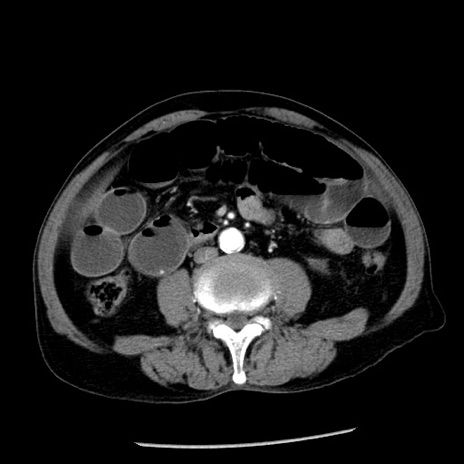

症例26(横断像)

【症例】80歳代男性

【主訴】嘔吐

【現病歴】昨晩2回嘔吐あり、今朝になっても嘔吐あり。来院。

【既往歴】胃潰瘍

【身体所見】意識清明、BT 37.6℃、BP 166/95mmHg、HR 100bpm、SpO2 97%、腹部:平坦・軟、腸蠕動音聴取良好、圧痛なし。

【データ】WBC 21900、CRP 1.46